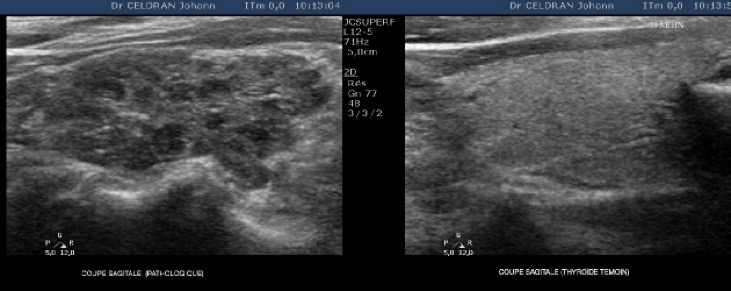

IMAGERIE

US: - de plus en plus hypoéchogène et hétérogène avec travées travées

- petites plages microkystiques (vermoulu)

- PSEUDO-NODULES